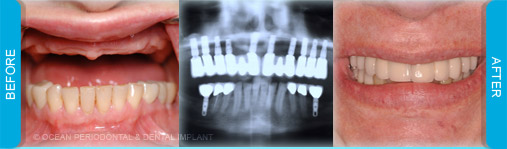

Dental implants are commonly used to replace missing or lost teeth in order to ensure patient comfort, function, and aesthetics. Indeed, there are many treatment options for management of missing teeth, such as bridges, and partial/complete dentures.

Nonetheless, numerous studies have demonstrated that implant-supported restorations are generally deemed to have superior functional and aesthetic outcomes. Furthermore, there are cases where dental implants may be the only logical choice for the restoration of function and aesthetics.

Dental implants can be used to replace missing teeth. There are many benefits to this type of treatment.